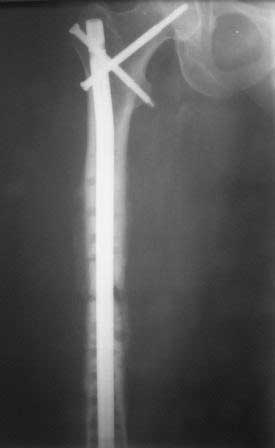

Результат нашего лечения: Произведено удаление пластины МIPO. Интрамедуллярный остеосинтез с рассверливанием канала. На 2-е сутки после операции больная передвигается при помощи костылей, с полной нагрузкой на оперированную конечность, болей в области перелома нет.

Фотографии в приложении.